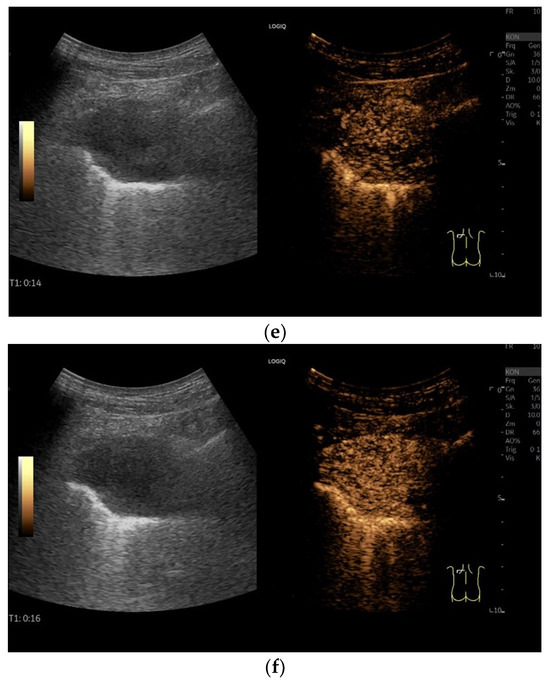

| Splenosis | Round, homogeneous lesions. Macrovessels on CDI are possible. Spleen-typical contrast behavior in CEUS with long-lasting contrast enhancement over several minutes. |

| Thoracal endometriosis | (Catamenial) hemothorax (and pneumothorax). |